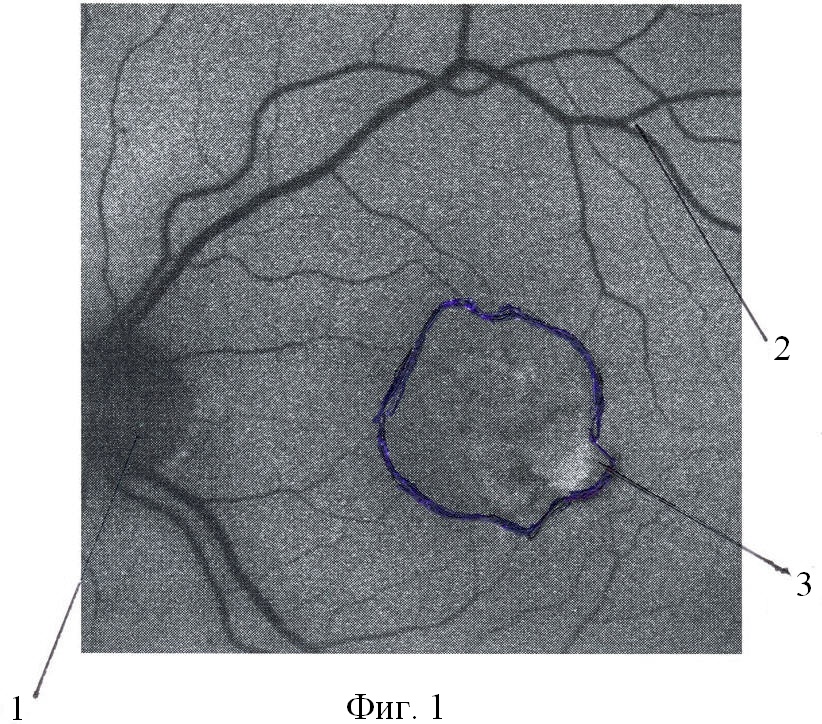

На Фиг.1 – вид первого контура зоны повышенной аутофлюоресценции, на Фиг 2 – вид второго контура зоны повышенной аутофлюоресценции.

Позицией 1 обозначен диск зрительного нерва, 2 – сосуды, 3 – зона повышенной аутофлюоресценции

Предложенный способ осуществляется следующим образом. Первоначально возбуждают аутофлюоресценцию с помощью маломощного сине-зеленого аргонового лазера с длиной волны 488 нм. Барьерным фильтром выделятся свечение флюорохромов с длиной волны более 500 нм. Дополнительно используется интерференционный фильтр, подавляющий зеленую составляющую спектра возбуждающего лазера 514 нм и еще один интерференционный фильтр, подавляющий отражения от глазного дна возбуждающего излучения 488 нм. Далее определяют параметры аутофлюоресценции сетчатой оболочки: фиксируют сниженную аутофлюоресценцию диска зрительного нерва 1 (Фиг.1), сниженную аутофлюоресценцию сосудов сетчатой оболочки 2 (Фиг.1), повышенный уровень аутофлюоресценции клеток ретинального пигментного эпителия 3 (Фиг.1). Обводим контур зоны повышенной аутофлюоресценции и измеряем площадь этой зоны, которую обозначаем как площадь S1. Далее через интервал времени 3-6 месяцев проводят дополнительное исследование. Аналогично фиксируют сниженную аутофлюоресценцию диска зрительного нерва 1 (Фиг.2), сниженную аутофлюоресценцию сосудов сетчатой оболочки 2 (Фиг.2), повышенный уровень аутофлюоресценции клеток ретинального пигментного эпителия 3 (Фиг.2). Обводим контур зоны повышенной аутофлюоресценции и измеряем площадь этой зоны, которую обозначаем как площадь S2.